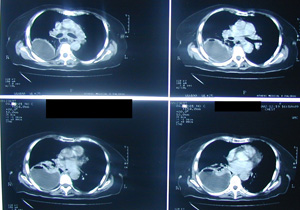

Εικόνα 2α-δ

Αξονική τομογραφία θώρακος σε διαφορετικά επίπεδα. Αναδεικνύει τα ίδια ευρήματα με την απλή ακτινογραφία και θέτει την διάγνωση της ρήξης της τραχηλικής μοίρας του οισοφάγου με εικόνα εμπυήματος του δεξιού ημιθωρακίου και εικόνα μεσοθωρακίτιδας με υδραερικό επίπεδο τόσο στο μεσοθωράκιο όσο και στον τράχηλο.